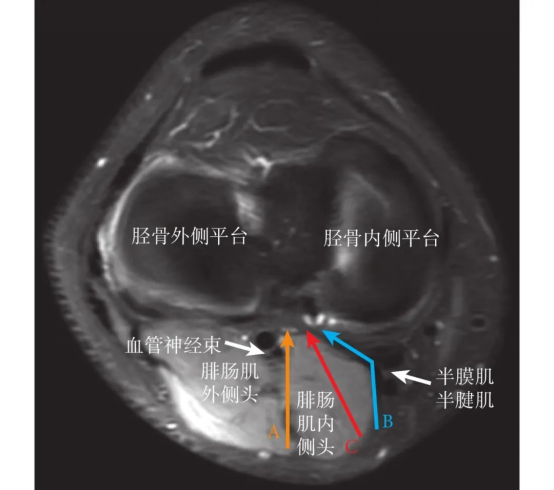

▲手术示意图(C为微创安全手术入路)

目前,PCL胫骨止点撕脱骨折的手术方式主要有切开复位固定、关节镜下复位固定和关节镜下PCL重建三大类,需根据患者的受伤时间、骨折性质、有无合并伤等具体情况制定个体化的治疗方案,以期最大限度恢复患者的膝关节稳定及功能,如何选择最佳治疗方式获取最好的临床疗效仍需根据术者的手术习惯和熟练程度并结合患者的具体情况进行决策。